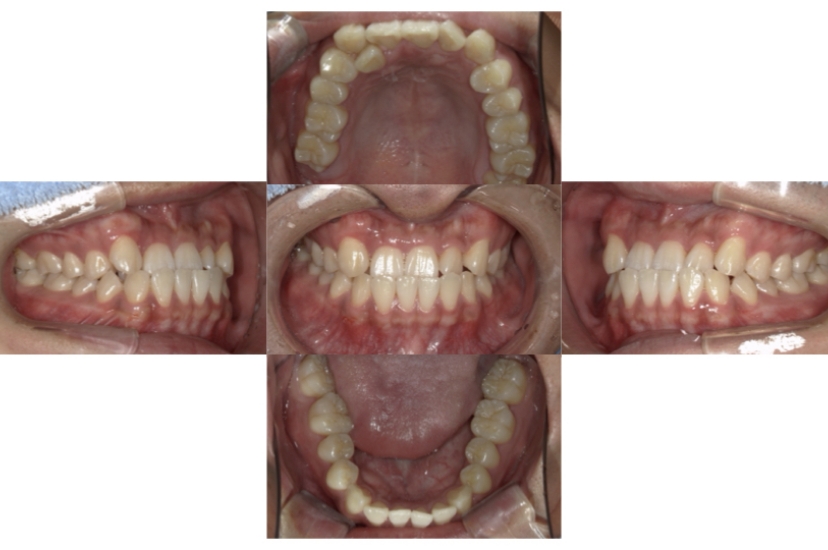

BEFORE

AFTER

上下顎前突、叢生(上下出っ歯、上下の前歯のガタガタ)のケースです。

装置はラビアル(上下表側)で、上下顎の小臼歯を4本抜歯を行っています。抜歯したスペースを使って、上下の前歯の後方移動と叢生(ガタガタ)の改善を行っています。

主訴 前歯のガタガタと口元がでているのが気になる。

年齢・性別 30歳 女性

治療方針 抜歯スペースを利用して上前歯の叢生(ガタガタ)と口元突出の改善

抜歯部位 上下顎左右第一小臼歯

使用装置 ラビアル(上下表側)、顎間ゴム

治療期間 1年11か月

治療回数 13回

リテーナー クリアリテーナー